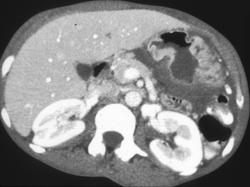

Gastric Lymphoma